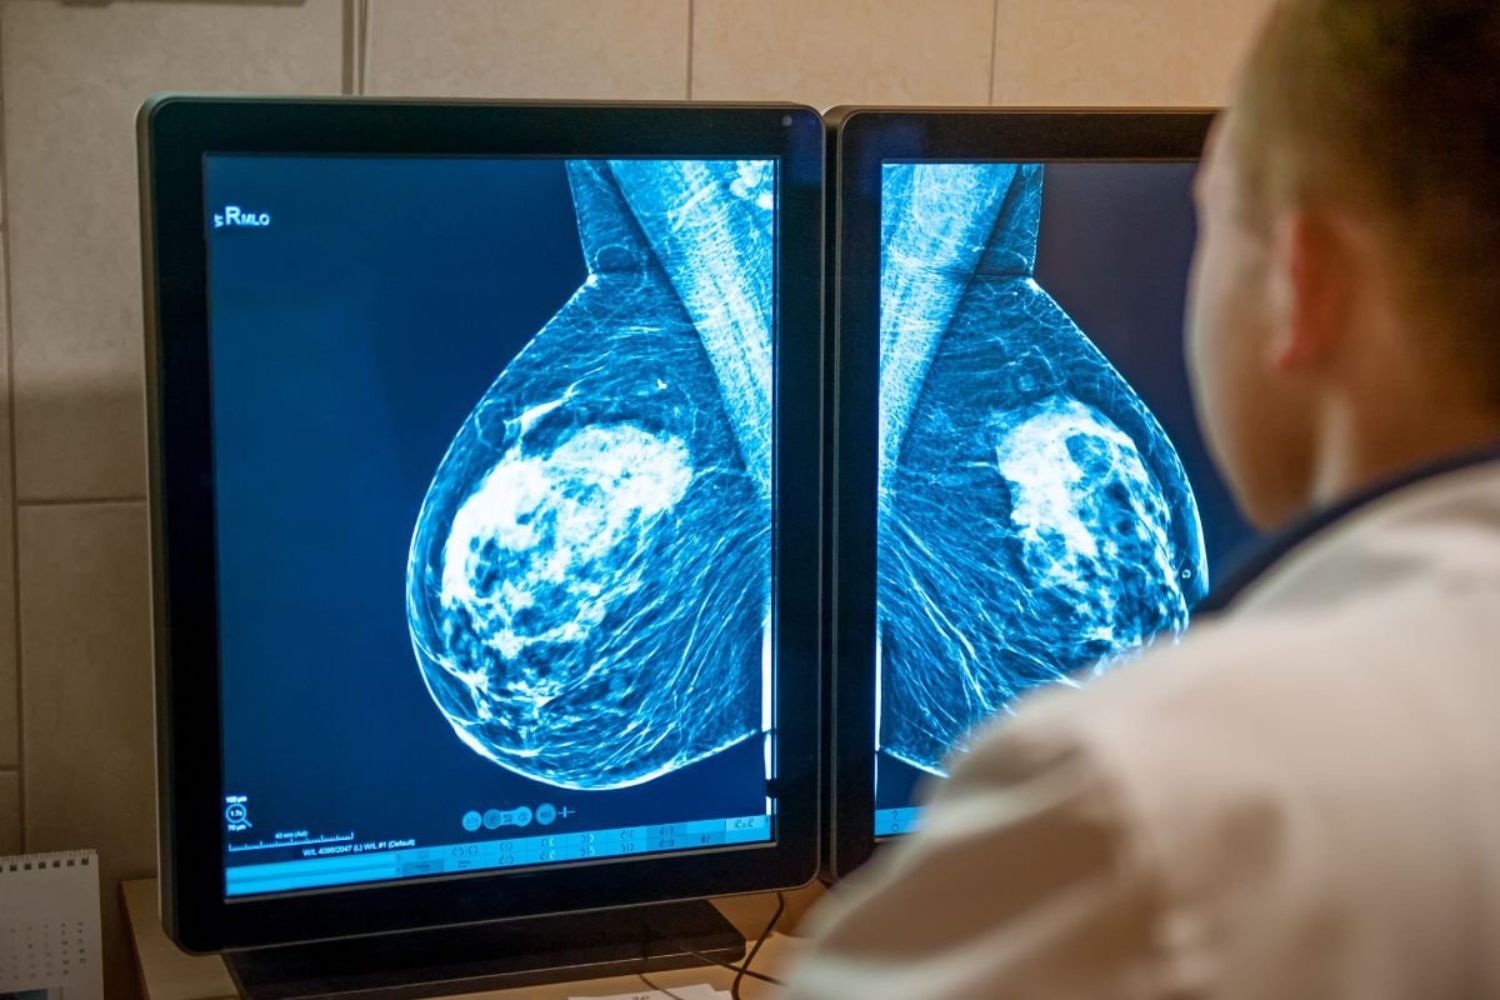

O que deveria ser apenas mais uma mamografia de rotina acabou se tornando um ponto de virada. Uma paciente, sem sintomas aparentes, participou de um projeto experimental que utilizava inteligência artificial como apoio na análise de exames.

A ferramenta utilizada no estudo foi projetada para identificar padrões extremamente sutis em exames de imagem. No caso das mamografias, isso significa detectar alterações mínimas que podem indicar o início de um tumor.

Esses sinais, muitas vezes invisíveis ao olho humano, são justamente o maior desafio da detecção precoce. E foi aí que a tecnologia fez diferença.

Após exames complementares, médicos confirmaram o diagnóstico: um tumor pequeno, em estágio inicial, que dificilmente seria percebido sem o auxílio da IA.